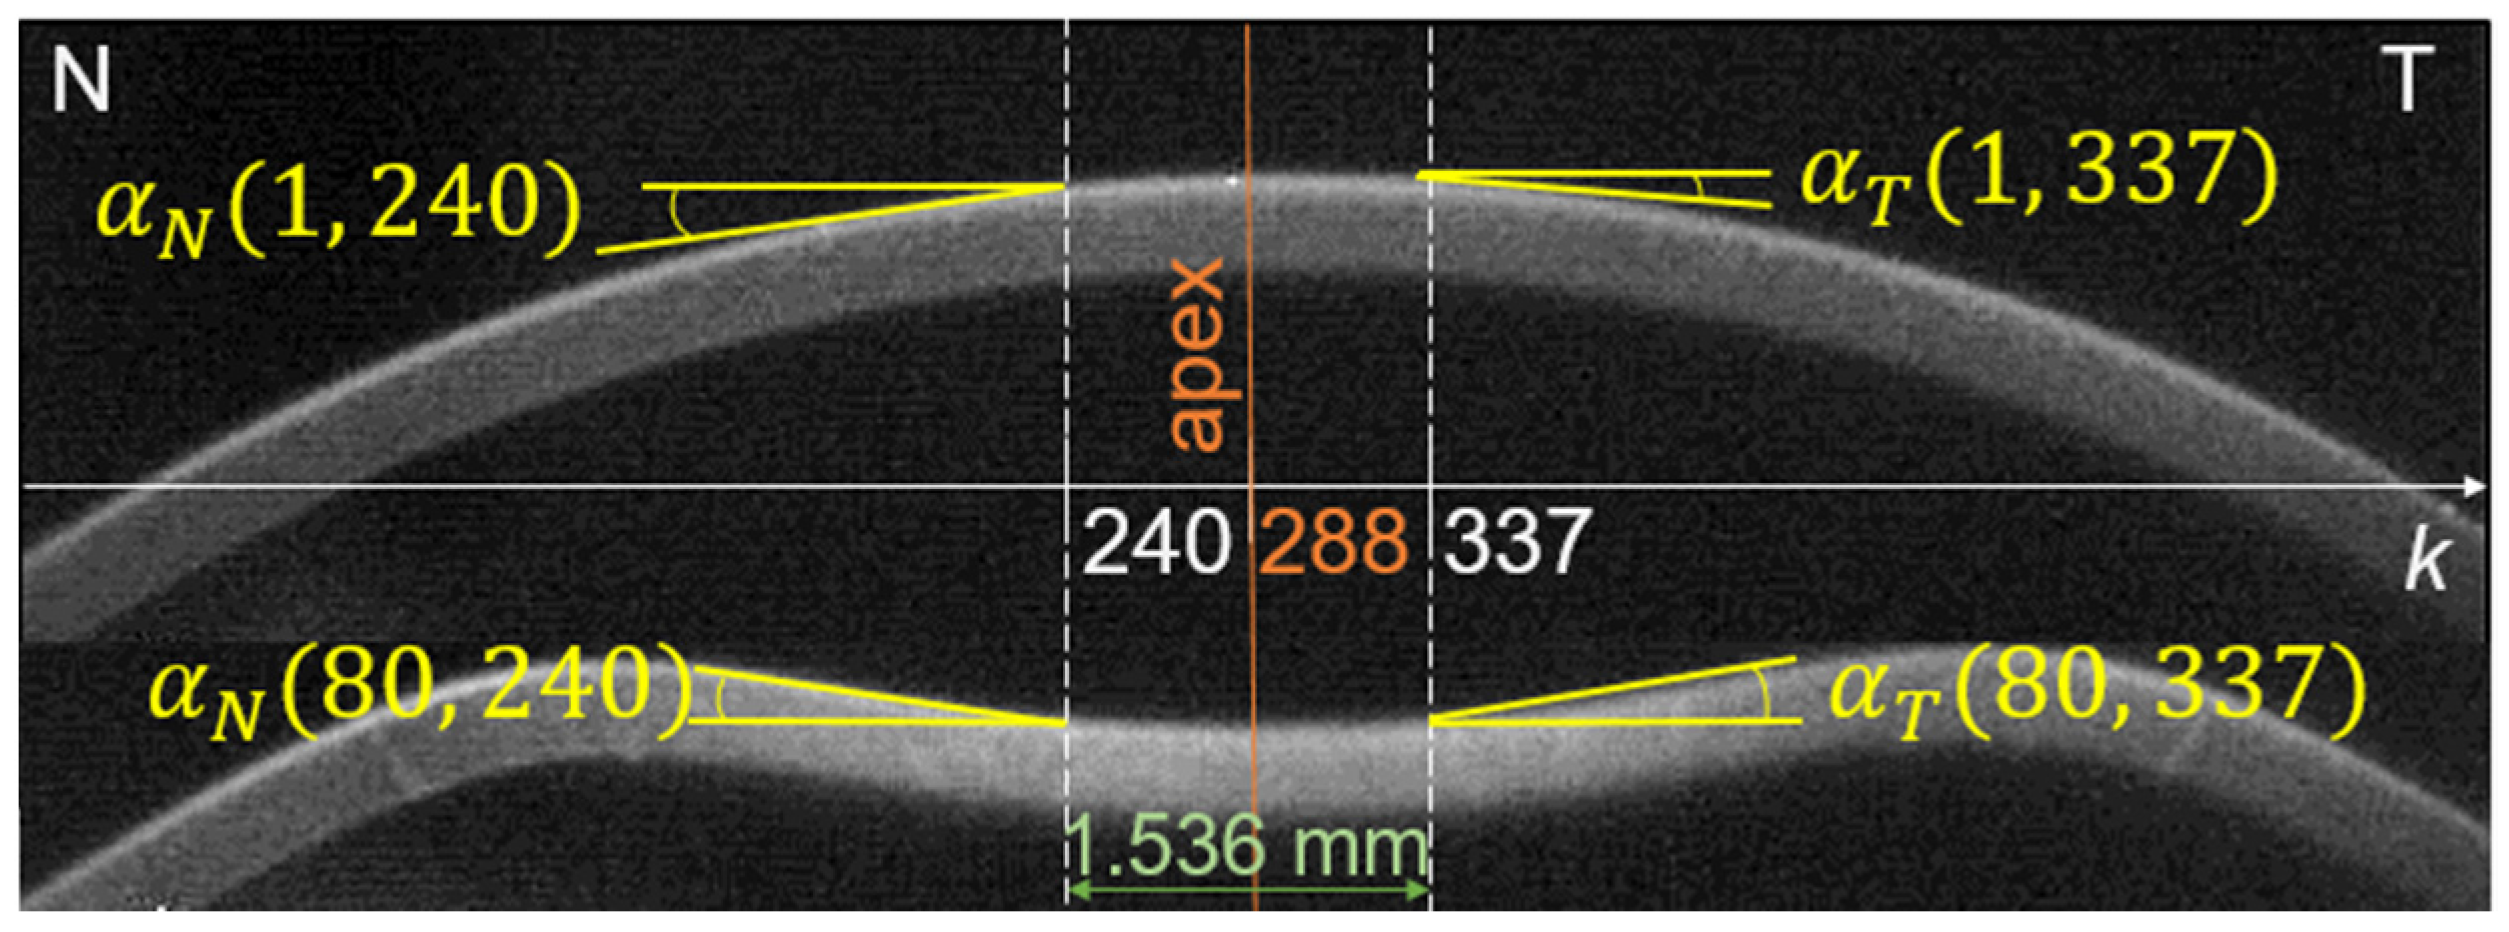

Since the largest changes due to air blast are observed in the central part of the cornea, our further analysis focused on this area. Two points located approximately 0.768 mm from the center on the nasal and temporal side were selected (corneal profile points falling on the 240th and 337th columns of images—see Figure 1). This choice has been made due to the high reproducibility and correlations of the proposed parameters referred to these points. Such a distance from the apex is large enough for clear observation of the mutual slope changes (low risk of numerical errors caused by too small mutual slope changes), yet much less than the minimum applanation lengths or peak distance along the corneal profile indicated by the tonometer software.

Figure 1.

Local slope of the corneal profile in the image columns k = 240 and 337 (points symmetrical to the apex on the nasal N and temporal T sides) at the beginning of the measurement (top image i = 1) and during the deformation (bottom image i = 80).